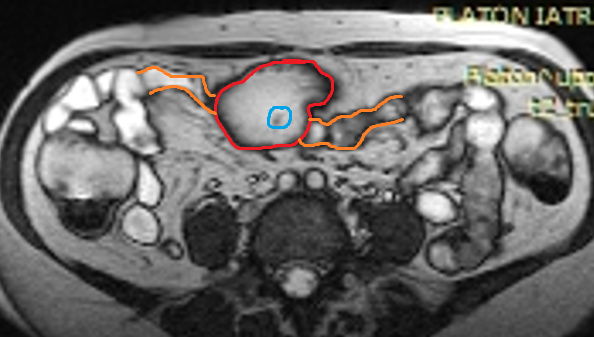

Abdominal CT scan. Red outline – Inflammatory fibroid polyp of the duodenum (Courtesy Dr. V. Penopoulos)